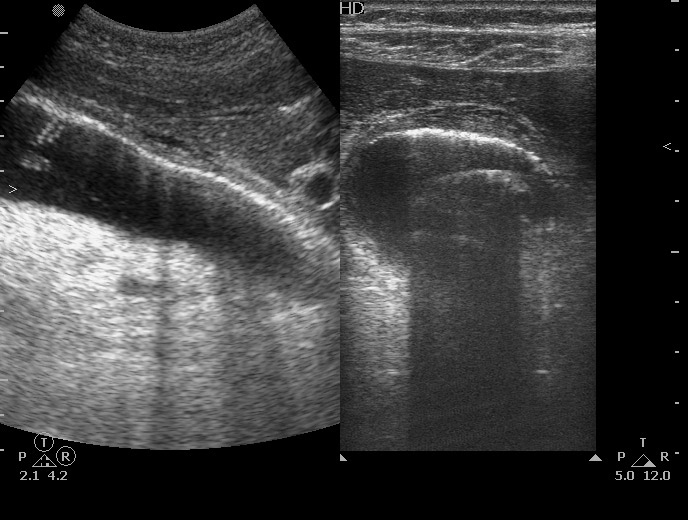

УЗИ: Острый эмфизематозный холецистит

Пожилой мужчина с болями по всему животу. Болеет 3-й день. Температура нормальная. Операций ранее не было.

Tags: acute emphysematous cholecystitis, ultrasonography, sonography

ЖКБ. Острый эмфизематозный холецистит.